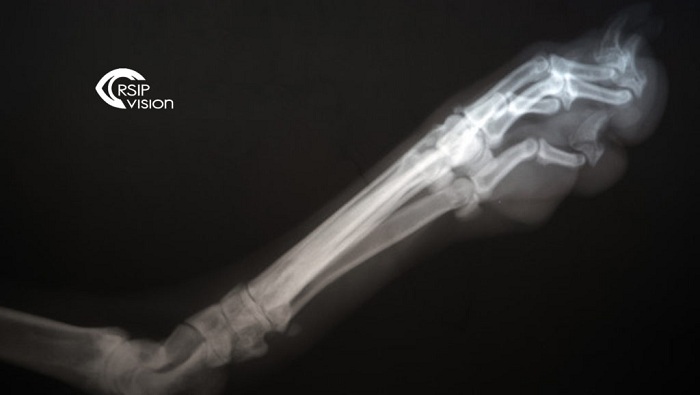

X-ray scanners are widely available and cheaper than CT or MRI scanners. Moreover, they expose the patients to much less radiation compared to CT scanners. However, X-ray images give only 2D information resulting from the summation of the 3D rays through the anatomical objects. As a result, doctors usually take two X-rays images of lateral and AP views for a rough estimate of the 3D anatomical structure. Nevertheless, what is still missing is a rich 3D modelling of each bone, which could provide critical data for surgery planning and implants fitting. The new technology developed by RSIP Vision generates a 3D model of the knee joint from two X-ray images of AP and lateral views.

The model is based on convolutional neural networks, a recent technique which have been proven to be very effective for various types of tasks. In particular, deep neural networks-based models outperform all previous approaches for image segmentation. However, 3D reconstruction from 2D images is still challenging for neural networks, due to the difficulty of representing a dimensional enlargement with standard differentiable layers. Reconstruction of bone surfaces in particular is extremely challenging, due to the transparent nature of the X-ray images. RSIP Vision addresses these challenges by introducing a special dimensional enlargement layer.